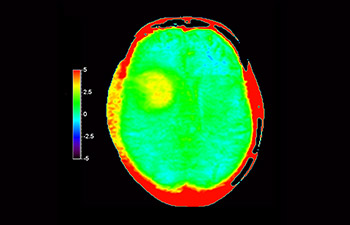

Glioblastoma

Brain with glioblastoma

with 3D APT

3D APT (Amide Proton Transfer) is a unique, contrast-free, brain MR imaging method addressing the need for more confident diagnosis in neuro oncology. 3D APT uses the presence of endogenous cellular proteins, to produce an MR signal that directly correlates with cell proliferation, a marker of tumoral activity. 3D APT can support trained medical professionals in differentiating low grade from high grade gliomas and, in differentiating tumor progression from treatment effect1.